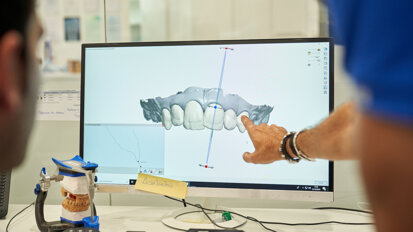

Użycie lasera Er:YAG i końcówek Precisio (Ryc. 11) w bardzo znacznym stopniu ułatwia nam pracę, którą wcześniej wykonywaliśmy nawet na kilku wizytach i niestety, nie zawsze z powodzeniem, co dla pacjenta często kończyło się resekcją wierzchołka lub nawet ekstrakcją zęba.